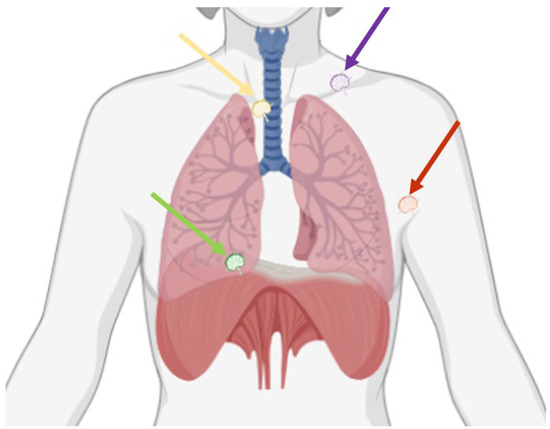

5. Pericardiophrenic Fat

5.1. Anatomy

5.2. Imaging

5.3. Surgical Resection